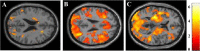

Results: Patients with PD performed significantly worse in terms of the correct answer rates of all n-back tests compared with HC. fMRI analyses performed during the 2-back test revealed reduced activation in the bilateral dorsolateral prefrontal cortex, middle frontal gyrus (MFG), and parietal lobule in the PD group compared with the HC group. In contrast, the fMRI result during the 0-back test showed only a marginal difference in the frontal lobe. On comparisons of task performance between the PD-MCI and PD-CN groups, we found that the correct answer rate in the 2-back test was lower in the PD-MCI group than in the PD-CN group. However, scores of the 0-back and 1-back tests were not significantly different between the two groups. The fMRI findings revealed that activations within the middle frontal gyrus (MFG) and inferior parietal lobule (IPL) during the 2-back test were reduced in the patients with PD-MCI when compared to those with PD-CN.

Conclusions: This study reports reduced activation of the MFG and IPL in patients with PD-MCI. These regions may be associated with the pathophysiology of working memory impairment in patients with PD, which involves fronto-striatal network dysfunction.